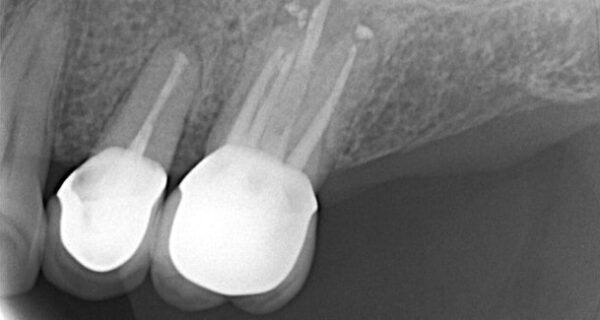

• การถ่ายเอ๊กซเรย์ฟิลม์เล็กเพื่อตรวจดูสภาพและรูปร่างของฟัน รวมถึงบริเวณที่มีการติดเชื้ออักเสบ

• ขั้นตอนการใส่เดือยฟันและครอบฟัน

• ฟันที่ได้รับการรักษารากฟันแล้วนั้นจะมีความแข็งแรงน้อยลง มีความเปราะบางมากขึ้น ดังนั้นการทำเดือยฟันและครอบฟันจึงมีความสำคัญเพื่อเพิ่มความมั่นคงแข็งแรงและช่วยปกป้องฟันซี่นั้น